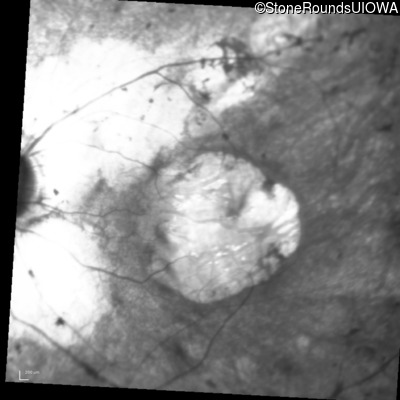

Age at visit: 15 years

This 15 year old male had a macular abnormality noted two weeks ago when he was refracted for his first pair of glasses. Bone spicule-like pigmentation was first noticed a year later (age 16) during a routine follow-up eye exam.